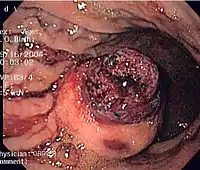

Endoscopic image of GIST in fundus of stomach, seen on retroflexion.

Same GIST seen on forward view of the endoscope showing overlying clot.

The definitive diagnosis is made with a biopsy, which can be obtained endoscopically, percutaneously with CT or ultrasound guidance or at the time of surgery. A biopsy sample will be investigated under the microscope by a pathologist physician. The pathologist examines the histopathology to identify the characteristics of GISTs (spindle cells in 70-80%, epitheloid aspect in 20-30%). Smaller tumors can usually be confined to the muscularis propria layer of the intestinal wall. Large ones grow, mainly outward, from the bowel wall until the point where they outstrip their blood supply and necrose (die) on the inside, forming a cavity that may eventually come to communicate with the bowel lumen.

When GIST is suspectedas opposed to other causes for similar tumorsthe pathologist can use immunohistochemistry (specific antibodies that stain the molecule CD117 [also known as c-KIT] see below). 95% of all GISTs are CD117-positive (other possible markers include CD34, DOG-1, desmin, and vimentin). Other cells that show CD117 positivity are mast cells.